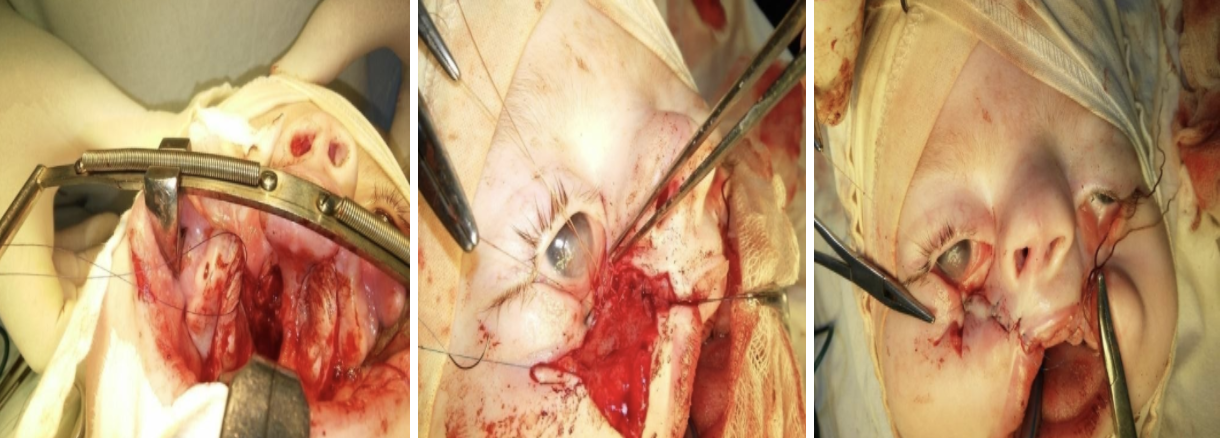

Двобічне косе незрощення обличчя (застосований принцип одномоментності)

Проведено дві операції

1-одномоментна пластика піднебіння, нижнього краю орбіти, альвеолярного відростку та середньої зони обличчя праворуч;

2- пластика середньої зони обличчя ліворуч.

Результат після 1-ї операції

2-га операція та результат

Інший приклад косого незрощення обличчя